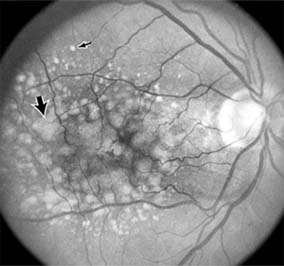

Nonexudative age-related macular degeneration is characterized by variable degrees of atrophy and degeneration of the outer retina, retinal pigment epithelium, Bruch's membrane and choriocapillaris. Of the ophthalmoscopically visible changes in the retinal pigment epithelium and Bruch's membrane, drusen are the most typical (Figure 10-1). Drusen are discrete, round, yellow-white deposits of variable size beneath the pigment epithelium and are scattered throughout the macula and posterior pole. With time, they may enlarge, coalesce, calcify, and increase in number. Histopathologically, most drusen consist of focal collections of eosinophilic material lying between the pigment epithelium and Bruch's membrane; they therefore represent focal detachment of the pigment epithelium. In addition to drusen, clumps of pigment irregularly dispersed within depigmented areas of atrophy may progressively appear throughout the macula. The level of associated visual impairment is variable and may be minimal. Fluorescein angiography demonstrates irregular patterns of retinal pigment epithelial hyperplasia and atrophy. Electrophysiologic testing in most patients is normal.

Figure 10-1

Figure 10-1: Age-related macular degeneration with discrete (small arrow) and large confluent (large arrow) macular drusen.